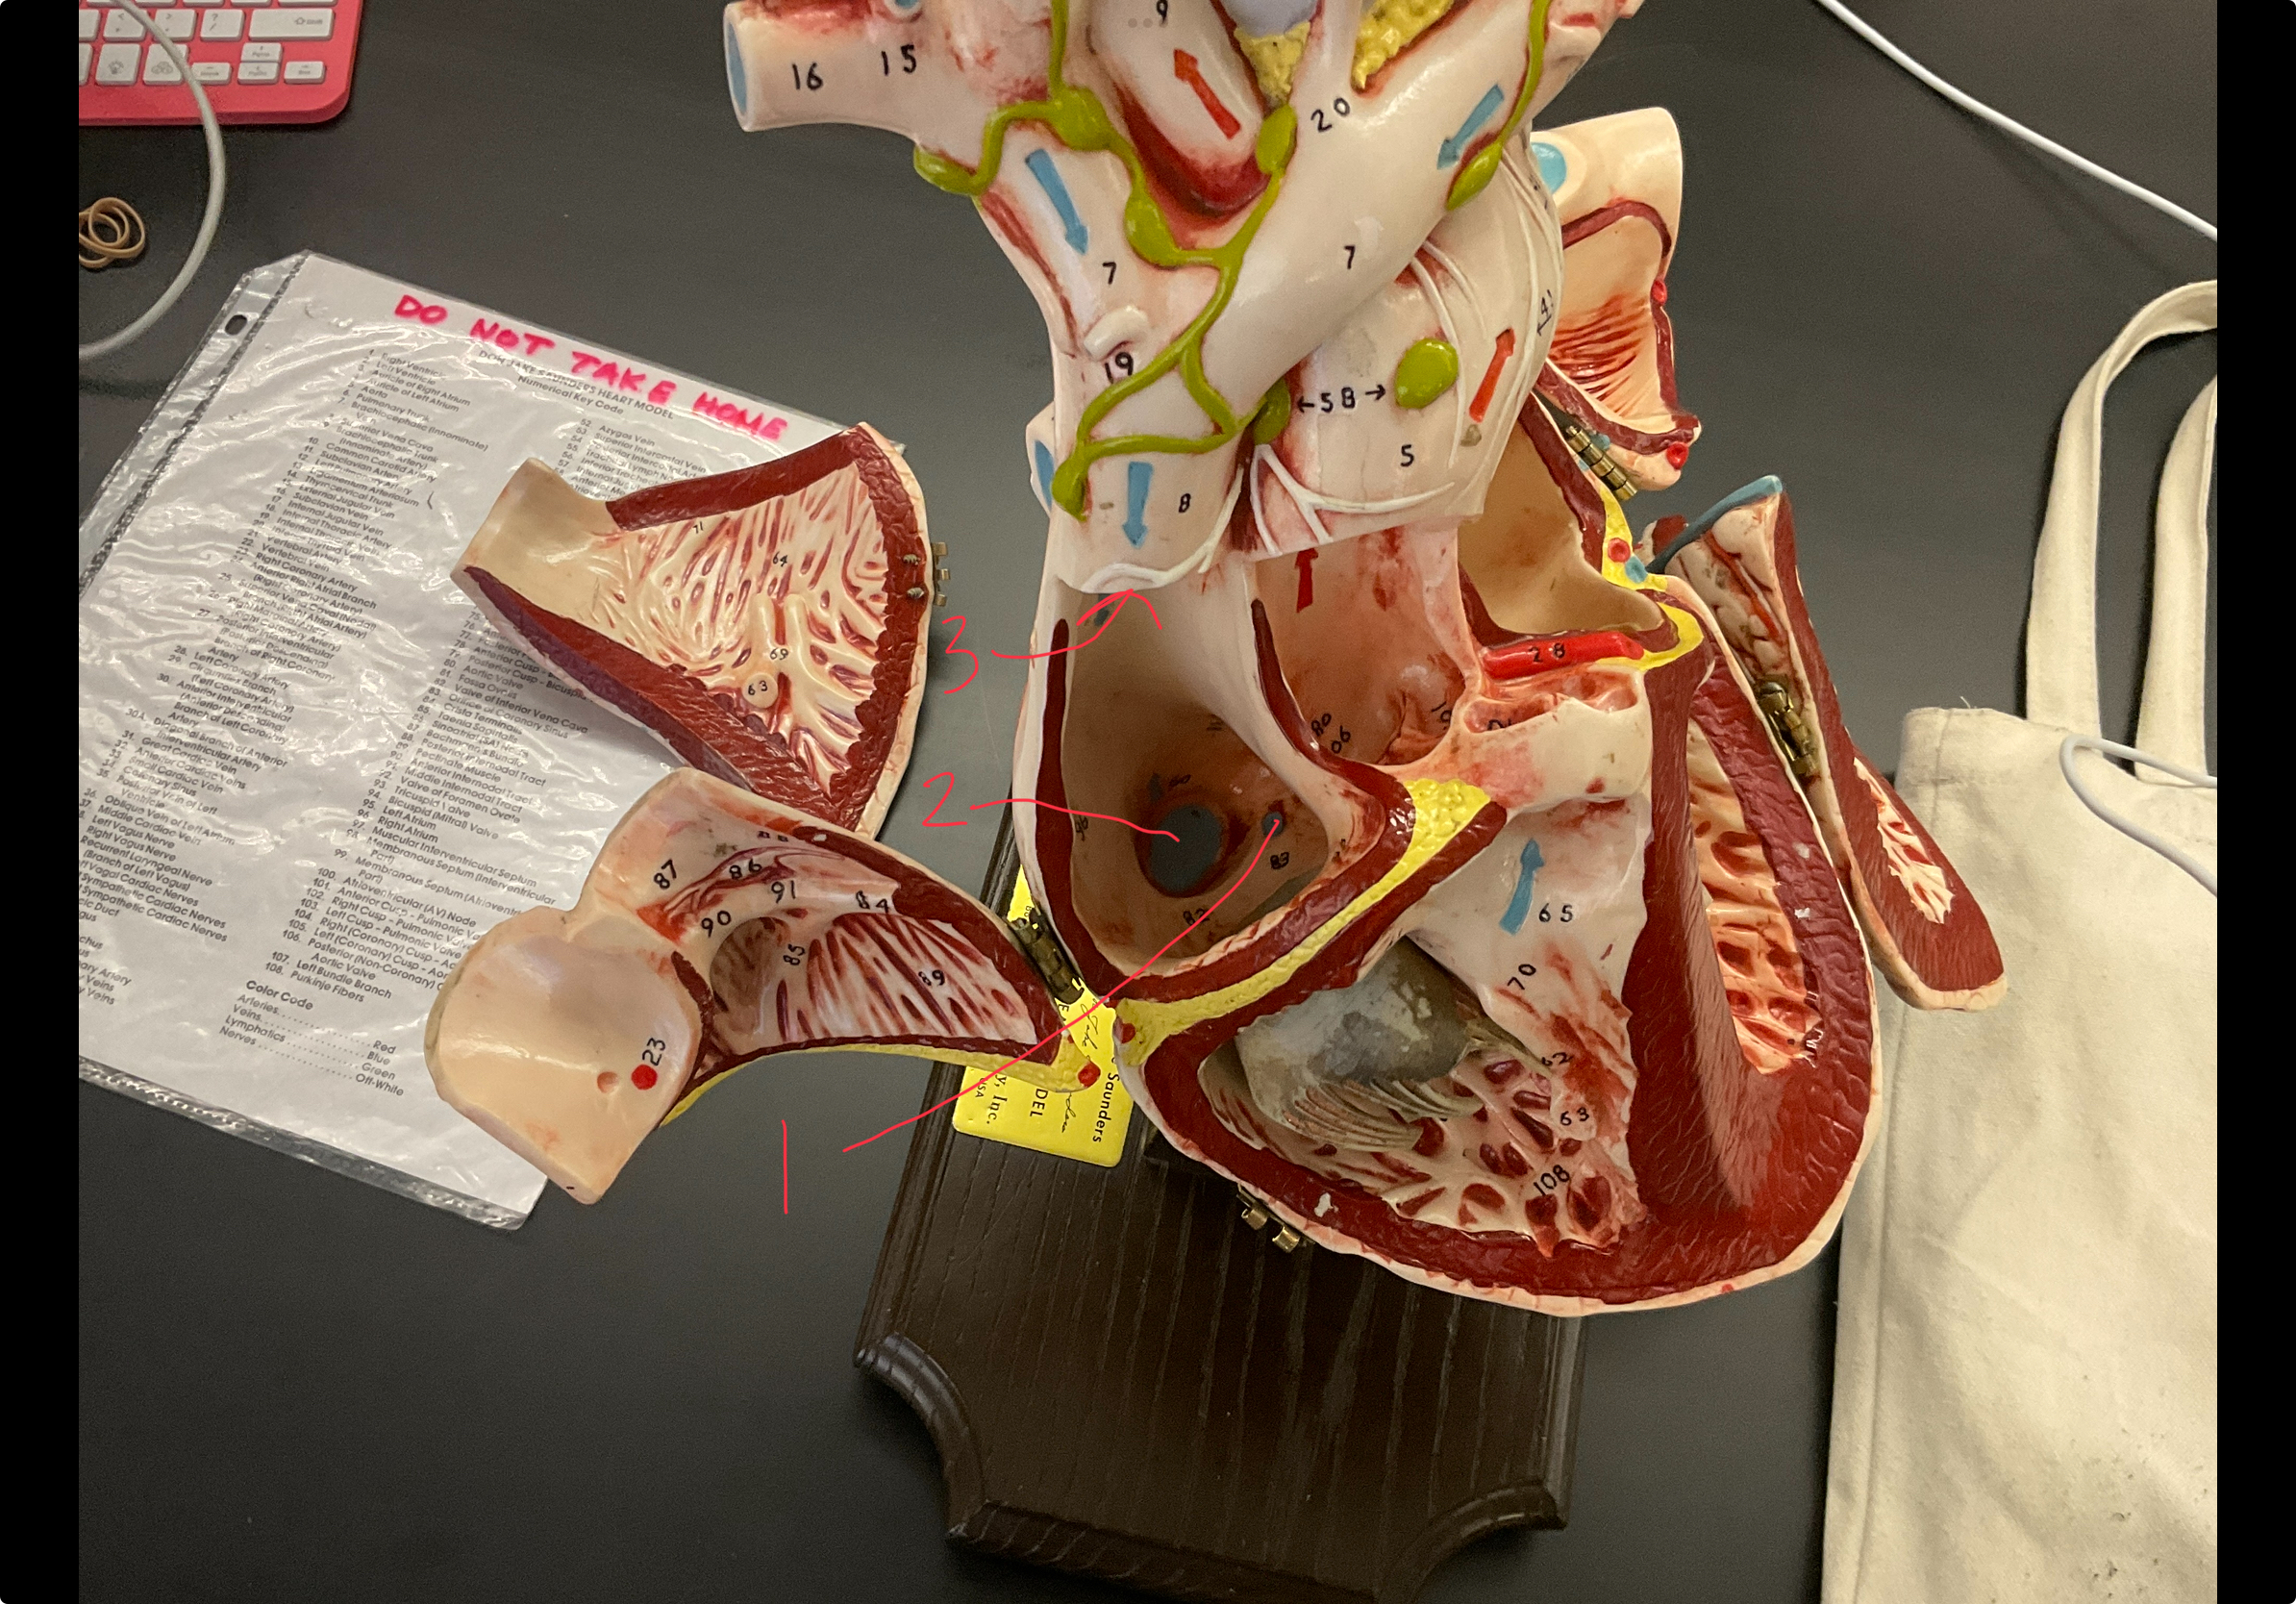

1

epicardium

2

3

endocardium

3

2

myocardium

4

1

coronary sinus

5

2

inferior vena cava

6

3

superior vena cava

1

right ventricle

8

2

left ventricle

9

3

bicuspid

10

4

tricuspid

11

5

interventricullar septum

12

6

left atrium

13

7

aorta

14

8

aortic trunk

15

9

pulmonary semi-lunar valve

16

10

atrevoventricullar sulus

1

papillary muscle

2

chordae tendineae

4

pulmonary trunk

aortic semi lunar valve

anterior inter ventricular sulcus

right coronary artery

circumflex artery

great cardiac vein

middle cardiac vein

coronary sinus

anterior inter ventricular artery

left pulmonary veins

left pulmonary artery

posterior interventricular sulcus

small cardiac vein